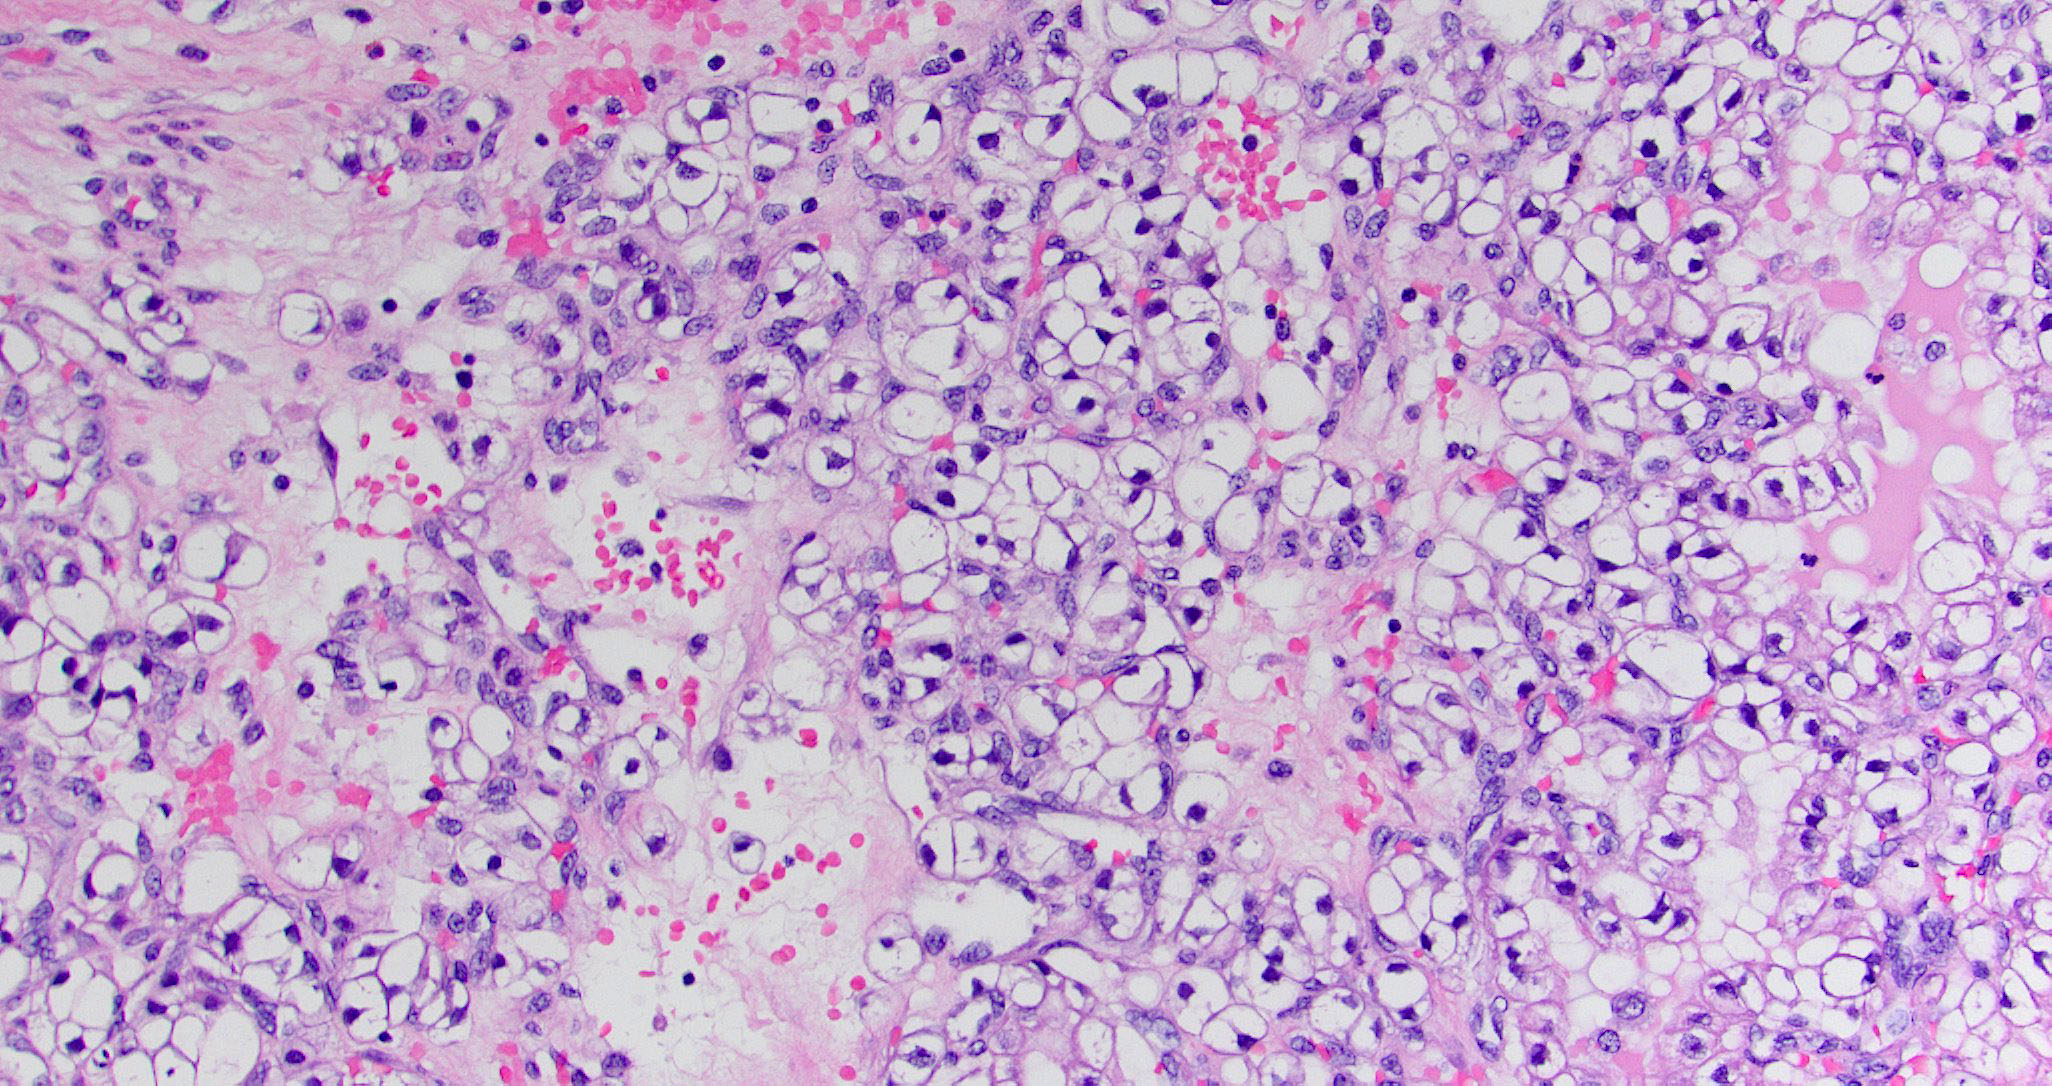

- Sinonasal renal cell-like adenocarcinoma (SRCLA) is a recently described (first case in 2002) subtype of low grade non-ITAC

- SRCLA exhibits uniform, cuboidal to polyhedral glycogen rich cells with clear cytoplasm that lacks mucin production (Head Neck Pathol 2016;10:68)

Microscopic (histologic) images

Contributed by Diana Bell, M.D.

Intestinal adenocarcinoma (ITAC)

Nonintestinal adenocarcinoma (non-ITAC)

Sinonasal renal cell-like adenocarcinoma

- Sinonasal renal cell-like adenocarcinoma

- Sinonasal renal cell-like adenocarcinoma

A 66 year old man presented with a rapidly growing soft mass on his glabellar region for 4 months. He was on medication for hypertension and recently had normal endoscopy findings for gastrointestinal malignancy. The findings of the transcutaneous open biopsy are given in the image shown above. What is the most likely diagnosis?

A. Intestinal type adenocarcinoma. Microscopy is similar to colonic adenocarcinoma but the latest screening endoscopy of the colon was normal. Answer B is incorrect because despite having a morphology similar to primary intestinal adenocarcinoma, the patient's recent gastrointestinal endoscopy was normal. Answer C is incorrect because no epithelium lined cystic mass is seen. Answer D is incorrect because there is no inflammation with polyploidal structure.

Board review style question #2

B. Kidney. As microscopy has clear cell architecture, it is crucial to rule out clear cell renal cell carcinoma. Answer A is incorrect because clear cell colorectal carcinoma is an extremely rare entity. Answer C is incorrect because clear cell carcinoma of the lung secretes mucus, which is absent here. Answer D is incorrect because the prostate does not have presentation as well as diagnosis of prostate cancer.